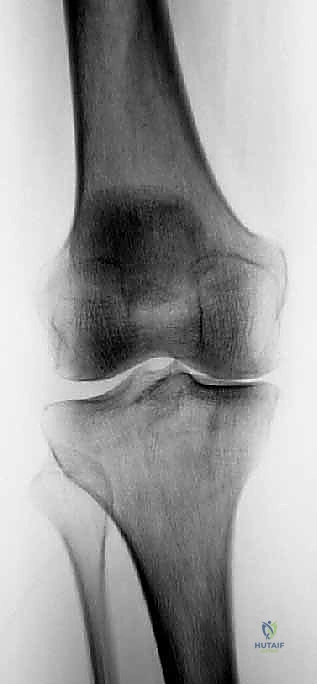

3. الأشعة السينية (X-rays) بوضع الوقوف: وهي الأداة التشخيصية الأهم. يتم أخذ صور أشعة والوزن محمل على الساقين لرؤية المسافة الحقيقية بين العظام. في حالة الخشونة المتقدمة، تظهر الأشعة غيابًا تامًا للمسافة المفصلية في الجزء الداخلي (Bone-on-bone).

صورة طبية: استبدال مفصل الركبة الجزئي (UKA): دليل شامل لمرضى خشونة الركبة الداخلية مع الأستاذ الدكتور محمد هطيف